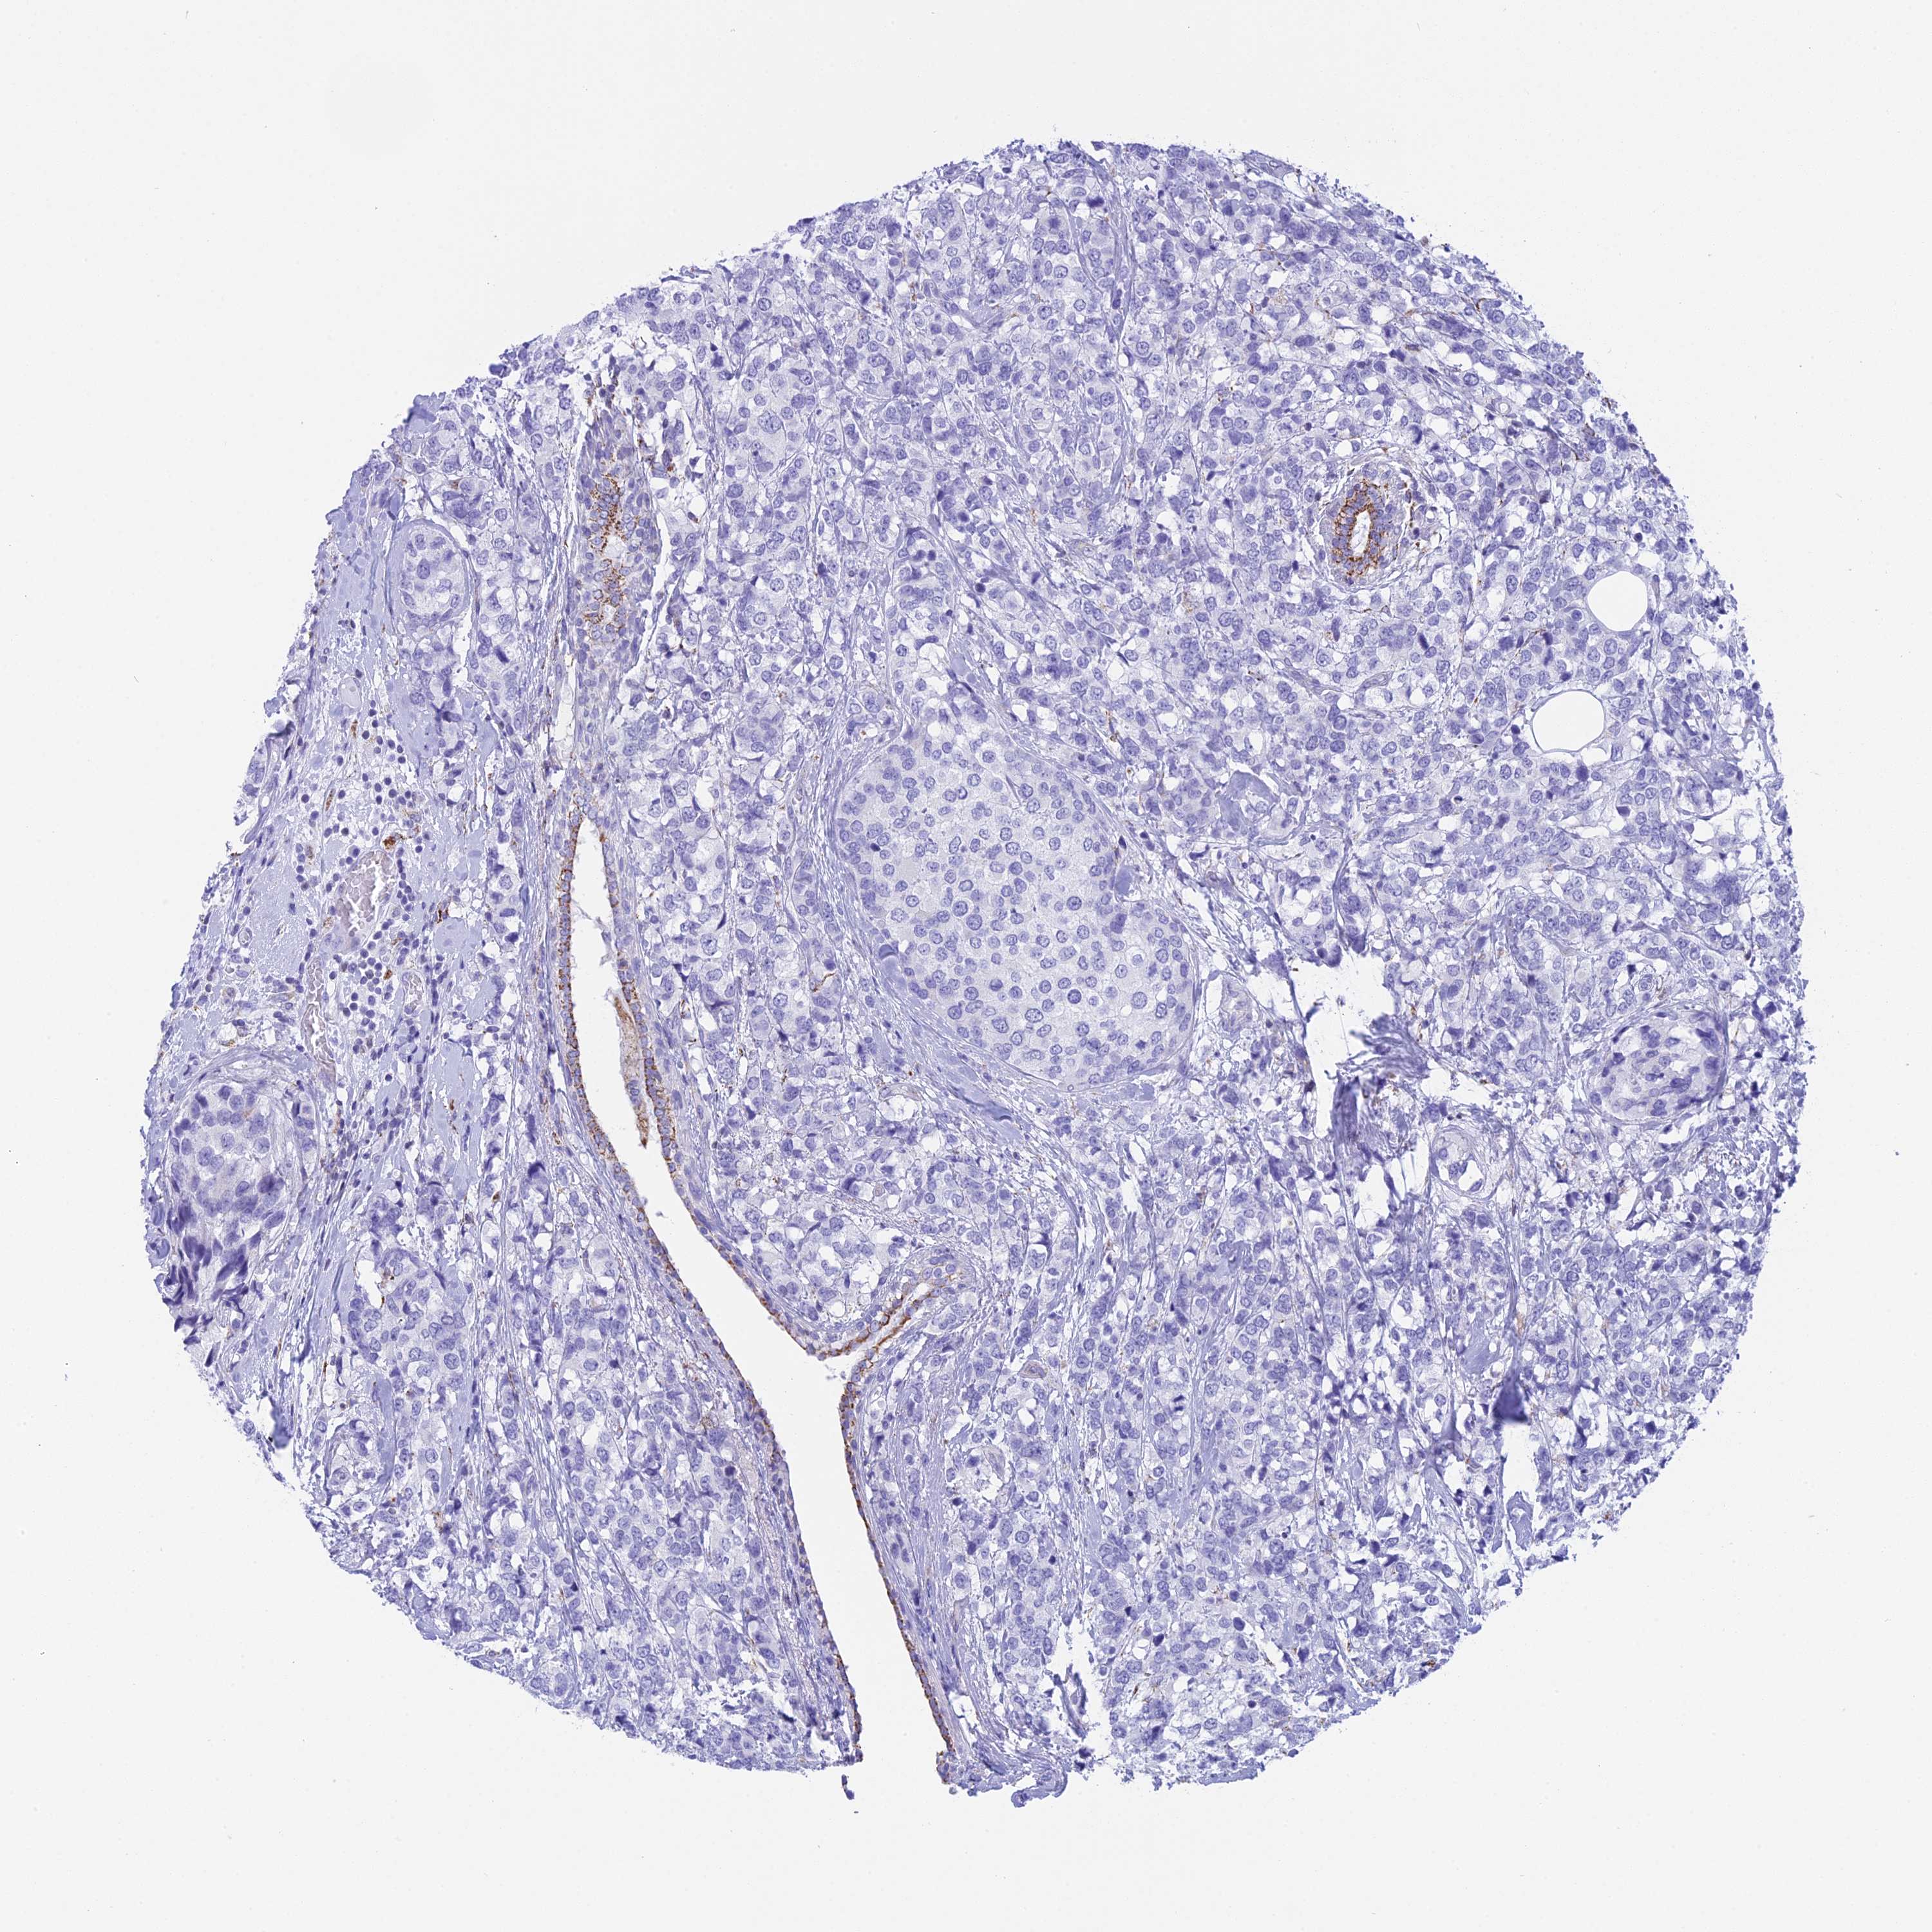

BRCA TCGA BRCA VALIDATION PROTEIN EXPRESSION

ANTIBODIES

AND

VALIDATION